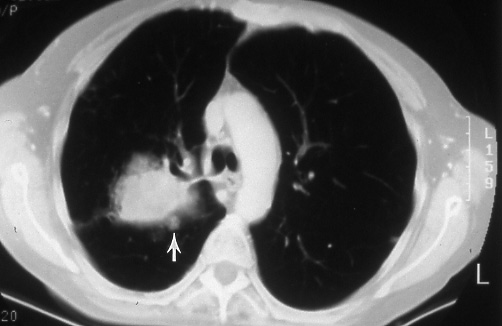

Fig. 20: Satellite nodule in primary tumor lobe. Computed tomographic scan showing a right upper lobe bronchogenic carcinoma with a small satellite nodule (arrow), T4.